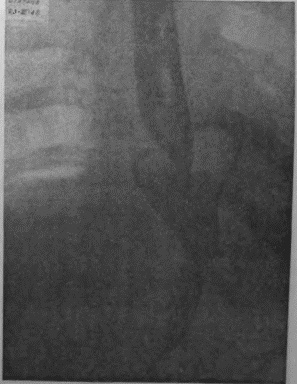

Если при локальном раке кардии и нижнего конца пищевода можно ограничиться все же экономной резекцией фундального отдела, то при более обширном раке или опухолях, захвативших немалую часть верхней трети малой кривизны, иногда возникает вопрос о целесообразности оставления антральной культи взамен тотальной гастрэктомии с трансторакальным соустьем пищевода и тощей кишки. Мотивы для этого могут быть двоякие. Первый и, конечно, главный — это радикальность самой резекции. Вопрос ставится так: да стоит ли сохранять антральный отдел желудка, рискуя, что в нем останутся пока еще невидимые раковые очаги; не вернее ли убрать весь желудок целиком и анастомозировать с тощей кишкой? Не создает ли тотальная гастрэктомия все же большую гарантию от рецидива? Я несколько раз видел отчетливую диссеминацию раковых узелков по передней и задней стенке желудка в радиальных направлениях, исходящую от строго локальной карциномы кардии. Это понуждало резецировать желудок в дистальном направлении весьма широко, оставляя лишь совсем маленькую антральную культю, которую удавалось все же подвести вверх в средостение и там легко анастомозировать с пищеводом тотчас ниже дуги аорты. На прилагаемых рентгенограммах (рис. 95—102) можно видеть, что небольшая культя желудка хорошо подтягивается кверху и прекрасно располагается в заднем средостении на месте иссеченного пищевода. Но каждый раз остается и тревожная мысль, как бы не получилось рецидива именно в этой сохраненной части желудка, поскольку рак проявил склонность к узелковому распространению по самой желудочной стенке. Второе соображение, которое выдвигает мысли о тотальной гастрэктомии, это опасение, что содержимое оставляемой дистальной половины желудка после пересечения обоих блуждающих нервов будет плохо эвакуироваться и тем доставит серьезные неприятности в ближайшем послеоперационном периоде. На моем личном опыте я пока еще не имел такого осложнения, но в нашей клинике однажды наблюдался больной, у которого эвакуация содержимого из оставленной антральной культи была чрезвычайно плохой в течение многих дней после операции. При этом создавалось впечатление, что полная атония оставленной части тела желудка сочетается с выраженным спазмом привратника, который не пропускал принятого бария в двенадцатиперстную кишку. Хотя, в конце концов, все наладилось и больной выписался в хорошем состоянии, однако тревог с ним было очень много. ![]() Рис. 95. ![]() Рис. 96. ![]() Рис. 97. ![]() Рис. 98. ![]() Рис. 99. ![]() Рис. 100. ![]() Рис. 101. ![]() Рис. 102. За сохранение антральной половины желудка и использование ее для прямого анастомоза с пищеводом говорит соблазнительно хорошая васкуляризация этой дистальной половины из сохраненных магистралей: аа. gastro-epiploica dextra et gastrica dextra. Насколько внимательно надо оценивать пригодность фундального отдела после лигирования обеих левых желудочных магистралей и всех vasa gastricae breves при самых высоких, надаортальных соустьях после экстирпаций среднего пищевода, настолько же после резекций проксимальной трети или половины желудка остающаяся дистальная часть превосходно васкуляризируется правыми артериальными магистралями. А это обстоятельство надежнее всего обеспечивает быстрое и прочное сращение по линии желудочно-пищеводного соустья, т. е. наиболее решающий этап всей операции. Мне могут возразить, что, анастомозируя пищевод с тощей кишкой, мы пользуемся органом, не менее богатым по кровоснабжению. Это верно, но поперечник тощей кишки не дает столько простора и пластического материала, сколько его имеется даже на короткой, но широкой антральной культе. Благодаря ширине культи имеется возможность после окончания двухрядного поперечного соустья укрыть дополнительно всю переднюю полуокружность анастомоза, сдвигая и сшивая над ним складки большой и малой кривизны. Прием этот чрезвычайно повышает прочность и герметизм соустья. А риск недостаточности последнего является главной опасностью всех подобных операций. При анастомозах с дистальной половиной желудка мы до сих пор осложнений еще не имели; зато три раза на десяток высоких резекций пищевода и анастомозов с фундальным отделом мы столкнулись с частичной недостаточностью соустья. В двух из этих случаев дело закончилось благополучно, и после вскрытия и дренажа ограниченных эмпием и срочного наложения подвесных энтеростомий для кормления пищевые свищи закрылись самостоятельно и довольно быстро. Но третий больной, врач 52 лет, хорошо перенеся надаортальную резекцию пищевода, постепенно угас, истощаясь из-за чресплеврального свища, получившегося вследствие недостаточности пищеводно-желудочного соустья. Повторяю, не только васкуляризация, но и форма оставляемой желудочной культи предопределяют качество и надежность анастомоза. Поэтому и при наложении раздавливающих гразеровских зажимов на желудок мы стремимся получить не длинную, узкую культю, а широкую, хотя бы за счет ее укорочения. Поднять высоко в средостение короткую культю можно без натяжения; зато ширина ее позволит сделать двойную боковую запашку поверх передней части законченного соустья с пищеводом. Чтобы еще уменьшить натяжение на линии анастомоза, после окончания последнего желудочную культю тщательно укладывают в заднее средостение и пришивают в нескольких местах к краям левой медиастинальной плевры. Наконец, совершенно обязательно пришить желудок к отверстию, оставляемому для него в ушиваемом разрезе диафрагмы. Напомню, что в самом начале операции, как только была вскрыта плевральная полость, n. phrenicus, всегда отчетливо видимый при переходе с перикарда на верхний купол диафрагмы, анестезируется инъекцией новокаина и раздавливается торзионным зажимом. Это создает неподвижность левой половины диафрагмы не только на время вмешательства, но и в течение нескольких месяцев после операции; таким образом, желудочная культя, вшитая в отверстие неподвижной диафрагмы, получает надежную опору и тем дополнительно исключается возможность натяжения в швах анастомоза. |